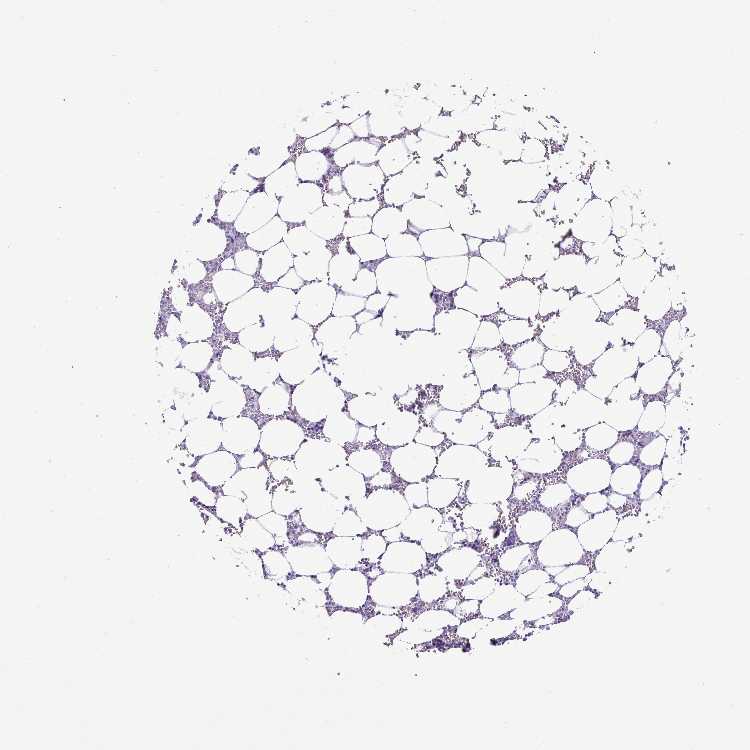

BONE MARROW - Antibody stainingi

Antibody staining in the annotated cell types in the current human tissue is reported as not detected, low, medium, or high, based on conventional immunohistochemistry profiling in selected tissues. This score is based on the combination of the staining intensity and fraction of stained cells.

Each image is clickable and will lead to virtual microscopy that enables deeper exploration of all samples and also displays staining intensity scores, fraction scores and subcellular localization as well as patient and tissue information for each sample.

Antibody HPA051880

Hematopoietic cells Not detected